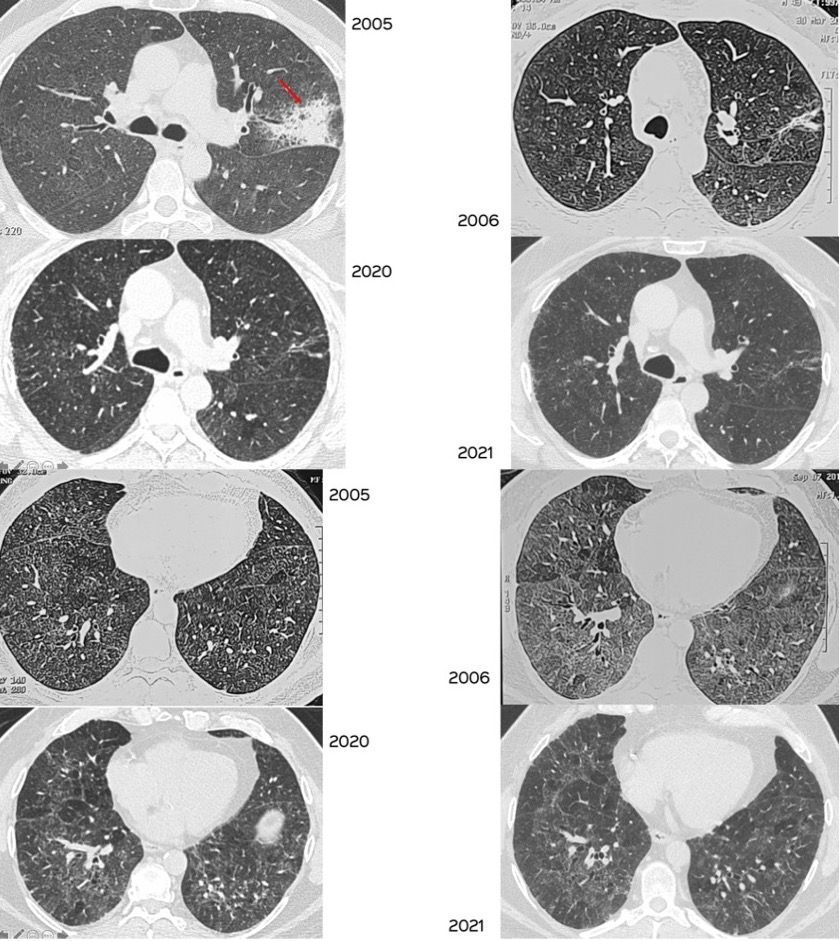

Case 29: The Slow Long Burn of Sarcoidosis Paid Members Public

The changing patterns of disease over 16 1/2 years in this patient with biopsy proven sarcoidosis